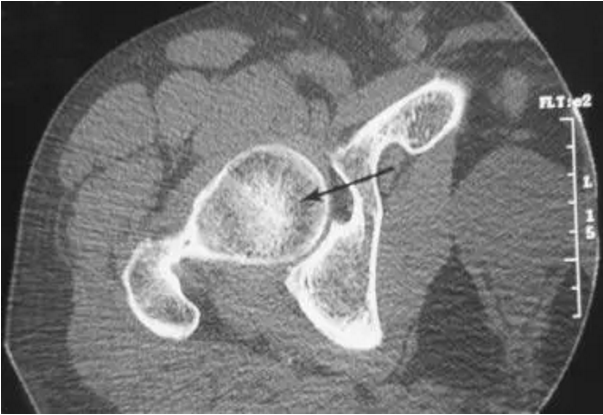

股骨头缺血坏死

对股骨头缺血坏死的患者CT显示股骨头的前部的骨折。 这个发现在轴向脂肪饱和的T2加权磁共振图像上被证明,但是由于CT扫描的优异的分辨率,使用CT扫描更清楚地描绘。